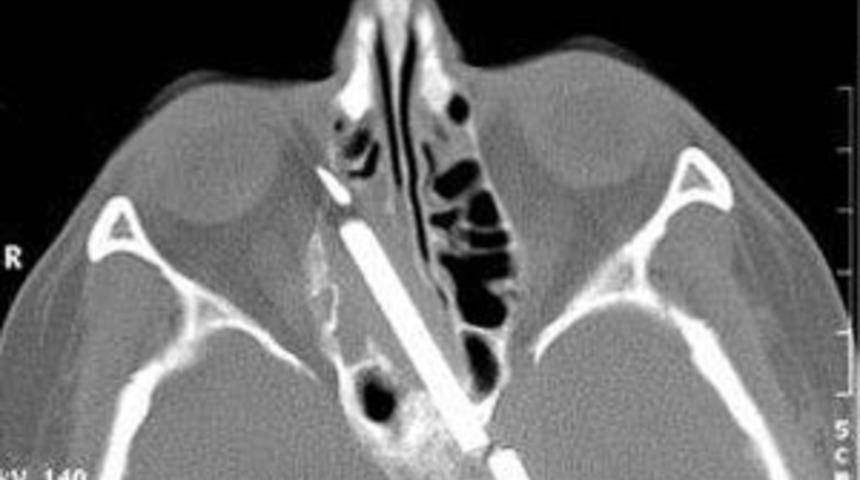

Melbourne'da sandalye ayağıyla saldırıya uğrayan bir adamın burnu kırıldı. Sandalye parçası da uzun bir operasyonla çıkarıldı